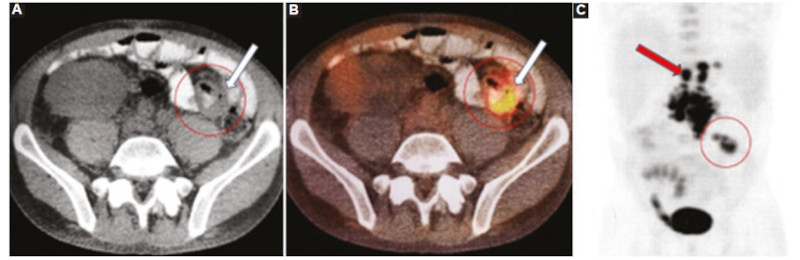

La región distal del intestino delgado es el sitio más frecuente de afectación del tracto gastrointestinal en el SLPT, seguido por el colon proximal, el estómago, el duodeno y el esófago28,34. Más de la mitad de los SLPT muestran compromiso del intestino delgado, aunque es rara la afectación aislada del tracto gastrointestinal, acompañándose en general de compromiso nodal, usualmente mesentérico35) (Fig. 4).

En cuanto a los patrones por imágenes en el SLPT del tracto gastrointestinal se describen el engrosamiento parietal circunferencial, siendo infrecuente que condicione una obstrucción al igual que los demás procesos linfoproliferativos; la dilatación intestinal aneurismática; ulceraciones; invaginaciones de segmentos cortos e imágenes polipoides conformando masas excéntricas11,28,36 (Figs. 5 y 6).

La presentación clínica del compromiso gastrointestinal suele darse con dolor abdominal difuso, vómitos, diarrea, fiebre y raramente con hemorragia digestiva35.